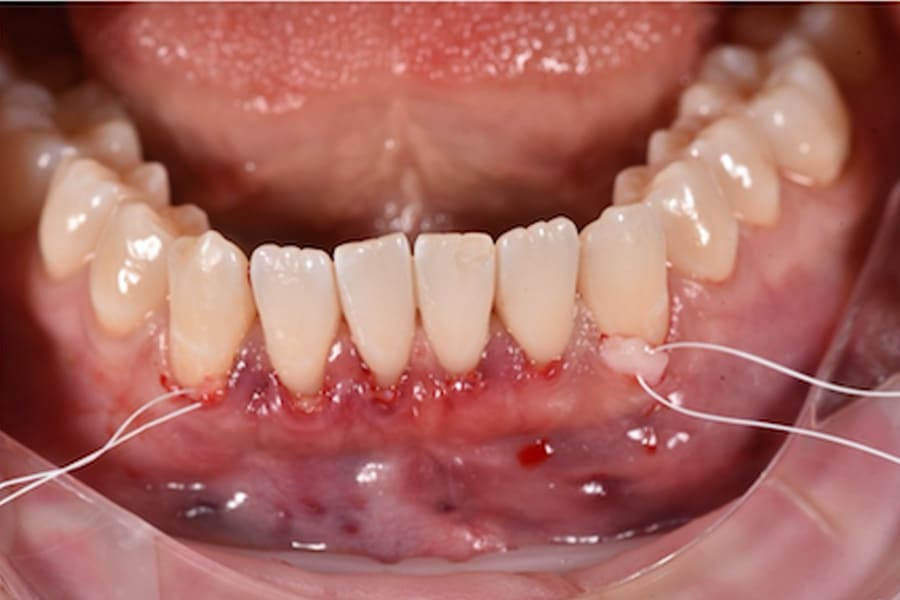

Periodontal Management and Thin Phenotypes

In thin phenotypes with early recessions, minimally invasive tunneling with CTG (with enamel matrix proteins on exposed roots when indicated) can increase soft-tissue thickness and support long-term stability after orthodontic tooth movement.12-16 (Figure 14 through Figure 17)